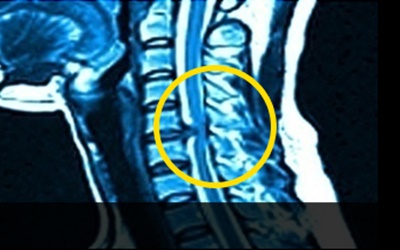

이를 의학계에서는 경추 추간판 탈출증이라고 한다고 하고요. 경추와 뼈들 사이에 존재하고 있는 물렁한 뼈조직이 있으며, 이를 디스크라고 하더라고요. 문제가 되는 것은 이 디스크가 외부로 탈출해서 신경을 압박하면서 통증이 시작되어요.

목디스크 증상은 거의 퇴행성 질환으로 4050대에서 천천히 증상이 생기는 경우가 두둑한데요. 꼬이게된 생활습관이나 오랜 시간 앉아있으면 비집고 나온 수핵이 척수를 압박해 신경을 누르게 되어 통증을 즐기고요. 손에 힘이 빠지고 저리다가, 다리까지 힘이 빠져 걷기 어려운 보행장애가 나타나게 돼요.